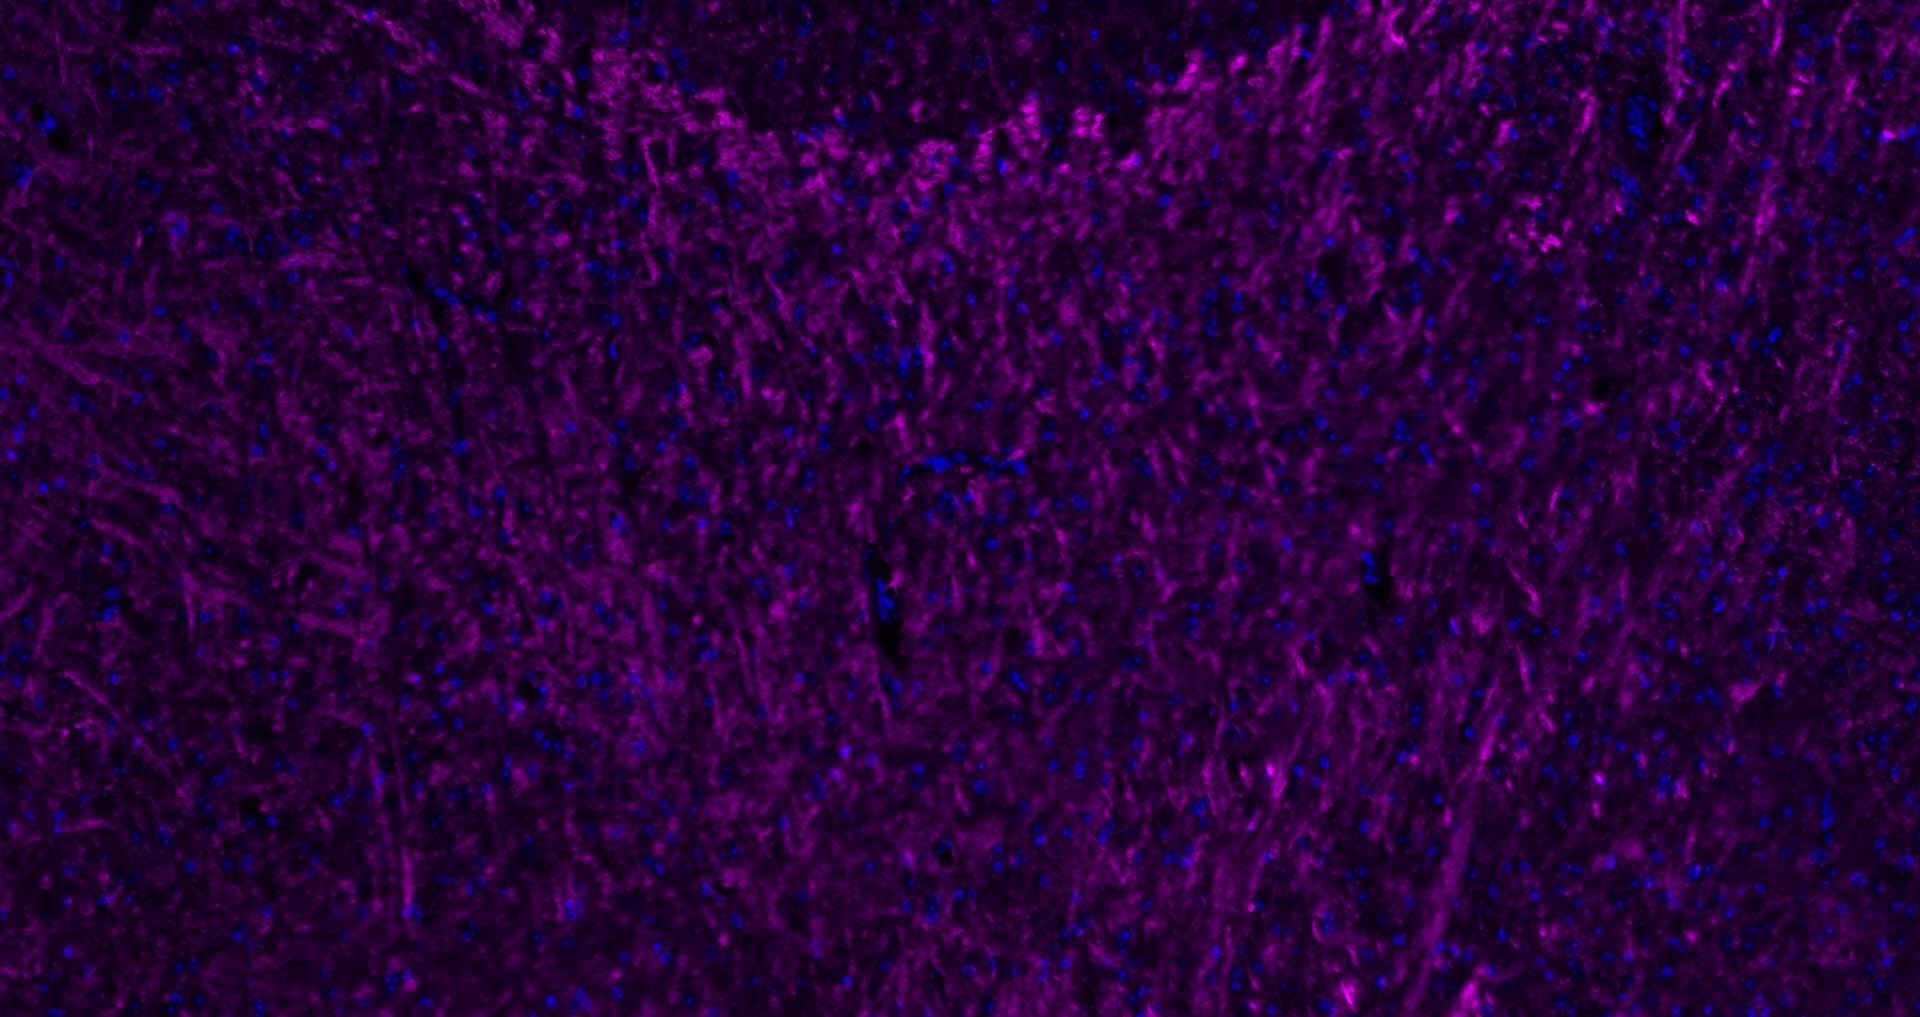

| Verified Activity | 1. Paraformaldehyde-fixed, paraffin embedded Rat Cerebellum; Antigen retrieval by boiling in sodium citrate buffer (pH6.0) for 15 min; Antibody incubation with MBP Polyclonal Antibody, Unconjugated at 1:200 overnight at 4°C. Followed by conjugated Goat Anti-Rabbit IgG antibody (Purple, TMAB-02007C5), DAPI (blue) was used to stain the cell nuclei.

2. Paraformaldehyde-fixed, paraffin embedded Human Cerebellum; Antigen retrieval by boiling in sodium citrate buffer (pH6.0) for 15 min; Antibody incubation with MBP Polyclonal Antibody, Unconjugated at 1:200 overnight at 4°C. Followed by conjugated Goat Anti-Rabbit IgG antibody (Purple, TMAB-02007C5), DAPI (blue) was used to stain the cell nuclei. 3. Paraformaldehyde-fixed, paraffin embedded Human Left Parietal Lobe; Antigen retrieval by boiling in sodium citrate buffer (pH6.0) for 15 min; Antibody incubation with MBP Polyclonal Antibody, Unconjugated at 1:200 overnight at 4°C. Followed by conjugated Goat Anti-Rabbit IgG antibody (Purple, TMAB-02007C5), DAPI (blue) was used to stain the cell nuclei. 4. Paraformaldehyde-fixed, paraffin embedded Mouse Cerebrum; Antigen retrieval by boiling in sodium citrate buffer (pH6.0) for 15 min; Antibody incubation with MBP Polyclonal Antibody, Unconjugated at 1:200 overnight at 4°C. Followed by conjugated Goat Anti-Rabbit IgG antibody (Purple, TMAB-02007C5), DAPI (blue) was used to stain the cell nuclei. 5. Paraformaldehyde-fixed, paraffin embedded Mouse Cerebellum; Antigen retrieval by boiling in sodium citrate buffer (pH6.0) for 15 min; Antibody incubation with MBP Polyclonal Antibody, Unconjugated at 1:200 overnight at 4°C. Followed by conjugated Goat Anti-Rabbit IgG antibody (Purple, TMAB-02007C5), DAPI (blue) was used to stain the cell nuclei. 6. Paraformaldehyde-fixed, paraffin embedded Human Duodenum; Antigen retrieval by boiling in sodium citrate buffer (pH6.0) for 15 min; Antibody incubation with CHGA Polyclonal Antibody, Unconjugated at 1:200 overnight at 4°C. Followed by conjugated Goat Anti-Rabbit IgG antibody (Purple, TMAB-02007C5), DAPI (blue) was used to stain the cell nuclei. 7. Paraformaldehyde-fixed, paraffin embedded Human Fundus; Antigen retrieval by boiling in sodium citrate buffer (pH6.0) for 15 min; Antibody incubation with CHGA Polyclonal Antibody, Unconjugated at 1:200 overnight at 4°C. Followed by conjugated Goat Anti-Rabbit IgG antibody (Purple, TMAB-02007C5), DAPI (blue) was used to stain the cell nuclei. 8. Paraformaldehyde-fixed, paraffin embedded Mouse Stomach; Antigen retrieval by boiling in sodium citrate buffer (pH6.0) for 15 min; Antibody incubation with CHGA Polyclonal Antibody, Unconjugated at 1:200 overnight at 4°C. Followed by conjugated Goat Anti-Rabbit IgG antibody (Purple, TMAB-02007C5), DAPI (blue) was used to stain the cell nuclei. 9. Paraformaldehyde-fixed, paraffin embedded Mouse Small Intestine; Antigen retrieval by boiling in sodium citrate buffer (pH6.0) for 15 min; Antibody incubation with CHGA Polyclonal Antibody, Unconjugatedat 1:200 overnight at 4°C. Followed by conjugated Goat Anti-Rabbit IgG antibody (Purple, TMAB-02007C5), DAPI (blue) was used to stain the cell nuclei. 10. Paraformaldehyde-fixed, paraffin embedded Rat Cerebrum; Antigen retrieval by boiling in sodium citrate buffer (pH6.0) for 15 min; Antibody incubation with NF-L Polyclonal Antibody, Unconjugated at 1:200 overnight at 4°C. Followed by conjugated Goat Anti-Rabbit IgG antibody (Purple, TMAB-02007C5), DAPI (blue) was used to stain the cell nuclei. ![]() ![]() ![]() ![]() ![]() ![]() ![]() ![]() ![]() ![]() |